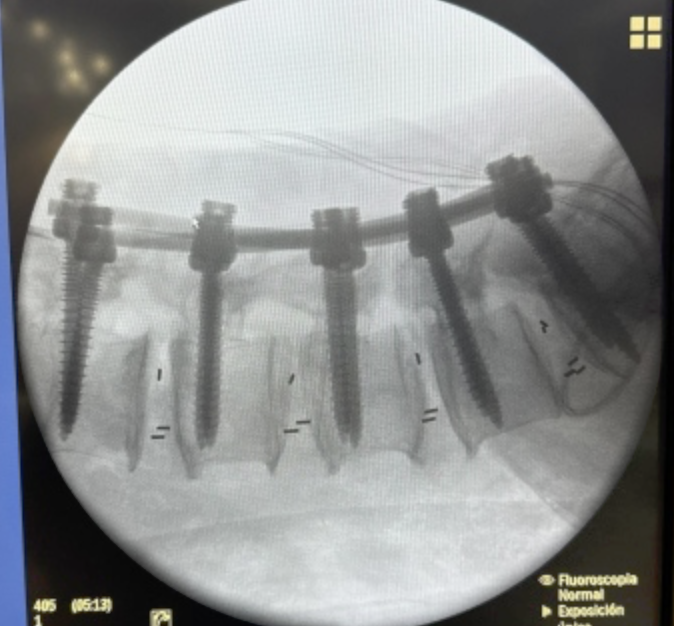

SURGERIES

RESULTS